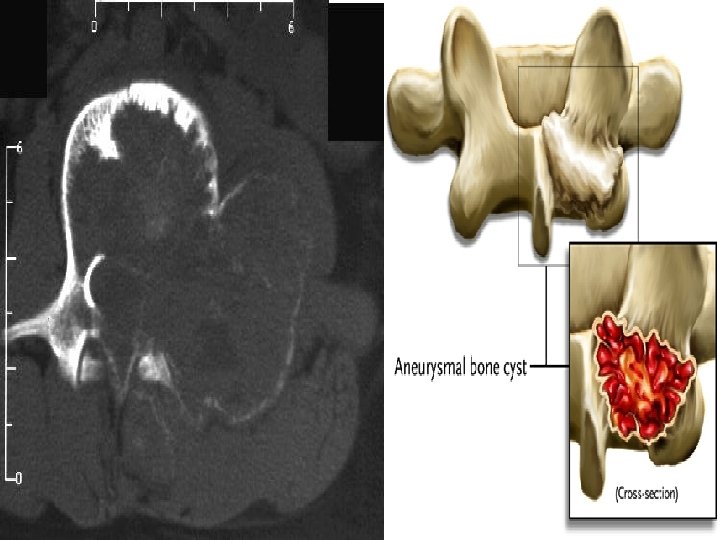

Aneurysmal Bone Cyst (ABC) • expansile lesion of bone containing thin-walled blood- filled cystic cavities Definition Etiology • (a) primary nonneoplastic lesion (2/3) • (b) arising in preexisting bone tumor (1/3): giant cell tumor (39%), osteoblastoma, chondroblastoma, solitary bone cyst, fibrous dysplasia, nonossifying fibroma, metastatic carcinoma • intraosseous arteriovenous malformation" with honeycombed spaces filled with blood + lined by granulation tissue / osteoid; areas of free hemorrhage Histology

Aneurysmal Bone Cyst (ABC) • INTRAOSSEOUS ABC : originating in bone Types: Age: marrow cavity. • EXTRAOSSEOUS ABC : posttraumatic hemorrhagic : cyst; originating on surface of bones • peak age 16 years (range 10 - 30 years) • Spine: with slight predilection for posterior elements Location: • long bones: eccentric in metaphysis of femur, tibia, humerus, fibula; pelvis

Respect epiphyseal plate soap-bubble Thin internal trabeculations Almost invesible cortex Expansile lesion No periosteal reaction except in case of fracture

Doughnut sign in scintigraphy

Aneurysmal Bone cyst : a. b. c. d. e. Occur secondary to fibrous dysplasia (√ ) Can present with scoliosis (√ ) May contain fluid-fluid level at MRI (√ ) Contain calcified matrix (X ) Doughnut sign at scintigraphy is pathognomonic (X )